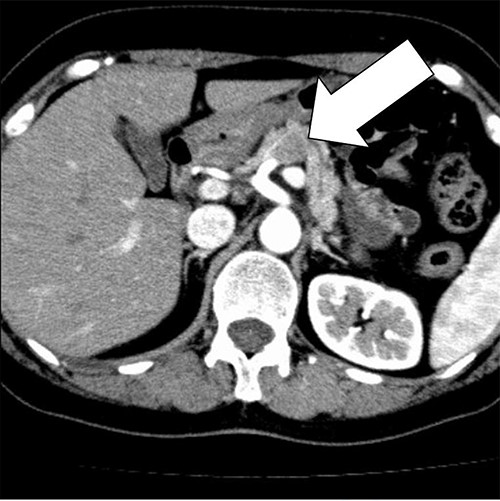

A 58-year-old woman began to have back pain and upper abdominal pain and then visited a hospital. Laboratory findings showed mildly elevated total bilirubin 1.3 mg/dl and high amylase 466 IU/l; however, peripheral blood, liver and kidney functions were within normal limits. Tumor markers were within normal limits: CEA 1.1 ng/ml, CA19–9 24.3 U/ml. An abdominal computed tomography (CT) scan revealed a 2-cm mass with mild contrast effect in the pancreatic body. There was a little tendency to invade the surrounding area, which was different from typical pancreatic ductal carcinoma (Fig. 1). Abdominal ultrasonography (US) showed a 19.4 × 12.6 mm mass in the pancreatic body. It was a hypoechoic mass with a clear boundary, smooth and homogeneous interior. Pancreatic duct dilation was observed more clearly than around the mass (Fig. 2).

Abdominal US showed a 19.4 x 12.6 mm mass in the pancreatic body. It was a hypoechoic mass with a clear boundary, smooth and homogeneous interior. Pancreatic duct dilation was observed more clearly than around the mass.